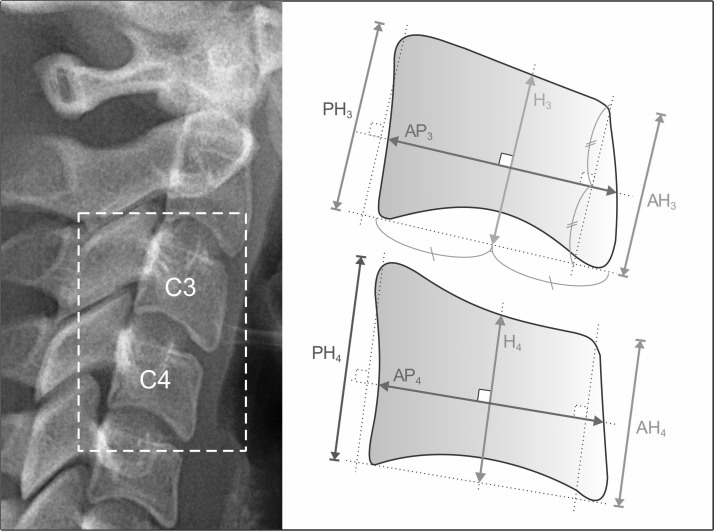

Digital lateral cephalometric and panoramic radiographs were obtained from the medical records of the Dental Hospital of Universitas Trisakti, Jakarta, Indonesia. We used the lateral cephalometric radiographs to develop the CV skeletal age estimation formula based on Mito and Sato’s (2002) method of measuring the parameters of anterior height (AH), posterior height (PH), antero-posterior height (AP), and body height (H) from C3 and C4 and then determining their ratios (AH/AP, H/AP, PH/AP, AH/H, H/PH, AH/PH) (Fig. 1). (12) We used panoramic radiographs to estimate dental age using the TCI, which calculates the coronal pulp cavity height (CPCH) and coronal height (CH) of the mandibular first premolar (Fig. 2). We selected the right or left region from the panoramic radiographs depending on which more clearly showed the pulp space as previously described. (5)

Figure 1.

The third and fourth cervical vertebrae bodies from cephalometric radiographs. The parameters were AH (Anterior Height), PH (Posterior Height), AP (Antero-Posterior Height), H (Body Height)